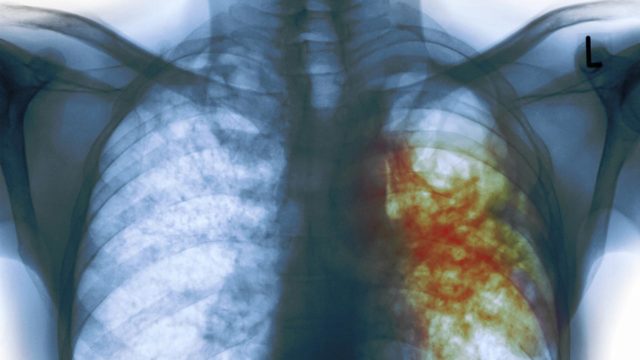

Nigeria moves to locate, enrol 200,000 undetected yearly TB cases

The Federal Government, yesterday, said the significant progress achieved in the last three years in the fight against tuberculosis (TB), Nigeria still records 200,000 new infections yearly.